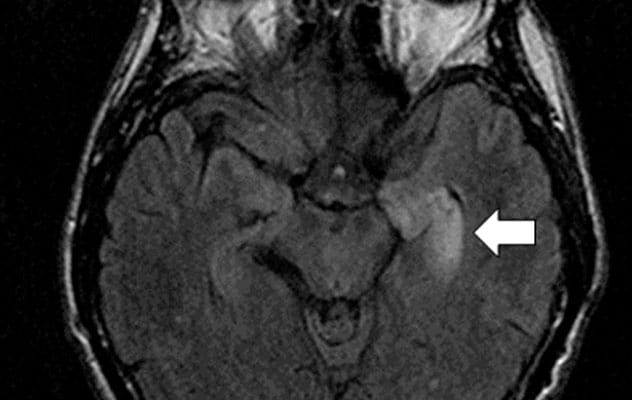

يُظهر التصوير المحوري للدماغ بالرنين المغناطيسي بتقنية استعادة الانعكاس الموهنة لإشارة السوائل لشخص مصاب بالخرف المناعي الذاتي والأجسام المضادة الذاتية LGI1 وجود فرط غير طبيعي في شدة T2 في الفص الصدغي الوسطي الأيسر (السهم)، وهذا يتوافق مع مرض التهاب الدماغ الحوفي.

MRI and EEG are used to exclude other causes of dementia and to help determine the specific type of autoimmune dementia that might be present. Laboratory evaluation of serum and cerebrospinal fluid also are critical. Mayo Clinic Laboratories offers both types of testing for autoimmune dementia.